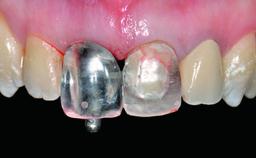

A 49-year-old female patient was referred for implant therapy to replace the upper right central incisor (tooth 11). The tooth had been assessed by an endodontist who diagnosed a vertical fracture of the root. The tooth had a hopeless prognosis and needed to be extracted. The patient was healthy and was not taking any medications. She was allergic to penicillin. The patient had high esthetic demands but her expectations were realistic. The extraoral examination revealed no facial asymmetries. The right temporomandibular joint demonstrated an opening click but was otherwise asymptomatic. The lip line was high with a significant gingival display.

Placement Protocol Early or late implant placement

Loading Protocol Conventional or early